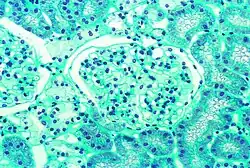

- Gewebeproben aus der Niere von Patienten mit Morbus Fabry

-

Diese lichtmikroskopische Aufnahme zeigt die Akkumulation von Gb3 in den Endothelien des Glomerulums, in den Mesangiumzellen, den Zellen im Interstitium und in den Podozyten. -

Ebenfalls eine lichtmikroskopische Aufnahme. In den Podozyten ist die erhöhte Ansammlung an Gb3 durch eine violette Anfärbung sichtbar gemacht worden. -